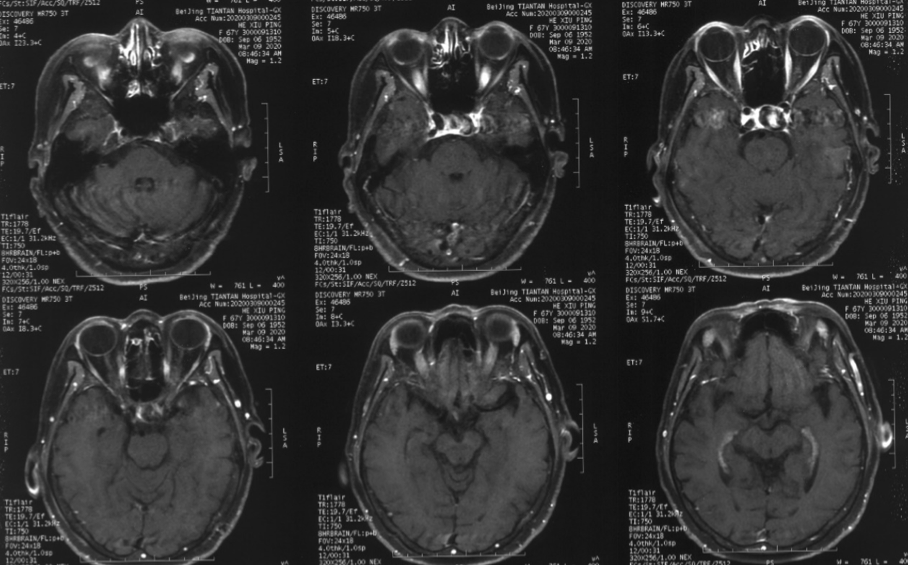

造影见左侧颈内动脉海绵窦段巨大动脉瘤,瘤体远端海绵窦水平段血管狭窄,眼动脉段血管扩张,左侧A1段缺如

本例患者动脉瘤位于海绵窦段,眼动脉段血管同时存在一定扩张异常,患者无明显高血压病史,从出血角度而言该患者相对出血风险并非极高。但根据核磁情况,尽管该动脉瘤位于海绵窦段,但已经有一部分瘤体突入颅内,一旦发生破裂出血,有一定可能进入蛛网膜下腔。且患者近期出现头晕及单眼黑朦,考虑与血流瘀滞于动脉瘤内有关。核磁上同样也可以看到瘤壁大量的血栓沉积,未来发生脑梗死的风险较大。此外,家属与患者对疾病的恐惧与治疗的决心也是我们最终决定施行手术治疗的原因之一。